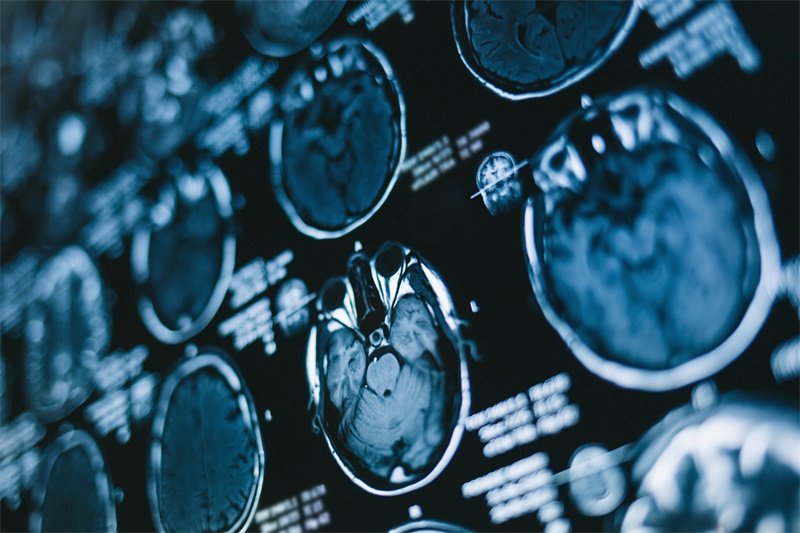

影像学检查如MRI或CT扫描是关键的辅助诊断工具。这些检查能够提供详细的脑部结构图像,帮助医生评估视神经及其周围的病变情况。